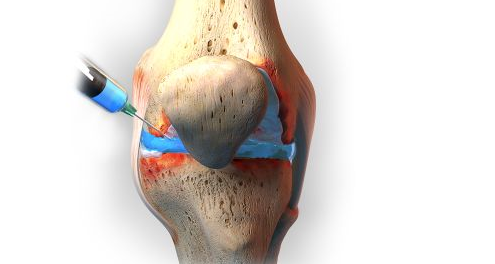

أي عملية جراحية في الجسم، تهدف إلى إصلاح الجزء التالف، وعملية جراحية تبديل مفصل الركبة في تركيا تهدف إلى استبدال الأجزاء المتضررة من مفصل الركبة والتي قد يكون سببها حمل في وزن الجسم، وحينها يتغير مفصل الركبة بأجزاء معدنية أو بلاستيكية تساعد على مرونة حركة المفصل بعد العملية، والخضوع بعد ذلك إلى بعض جلسات العلاج الطبيعي، والعلاج الطبيعي قد يساعد على علاج مفصل الركبه بدون جراحه والقضاء على الألم القدرة على المشي نتيجة ما قد حدث من تضرر لمفصل الركبة بشكل عام، وهو أمر شائع الحدوث لكل شخص يعاني من التهابات المفاصل أو الأربطة أو أي آلم في مفصل الركبة.

عند الخضوع للعملية الجراحية، تكون في بضع دقائق قليلة، وقد لا تزيد على ثلث ساعة، ويتم بدء العملية الجراحية هكذا:

– تعقيم منطقة الركبة

– عمل شق طولي بالجزء الأمامي من الركبة تقريبا 10 سم

– يتم استئصال الغضاريف التالفة وأيضا أي أطراف تالفة من العظام بمنطقة مفصل الركبة

– وضع مفصل ركبة صناعي مصنوع عادة من المعدن والبلاستيك المقوى

– تثبيت المفصل الجديد

– استخدام لاصق خاص تم صنعه مخصوص لهذا الغرض

وينبغي أن يكون داخل سطح المفصل الجديد بعض الثقوب الدقيقة التي تساعد على نمو العظام من خلالها من أجل ضمان ثبات المفصل بشكل جيد وصحيح، ويمكن علاج مفصل الركبة بالبلازما كبديل من هذا، وقد يتضمن تبديل مفصل الركبة بعض المخاطر أو بعض الأعراض جانبية محتملة وهي:

ونجد أنه هذ الطريقة تكون مبتكرة، حيث أنها تعمد على حقن المصاب بمَصلَين في الغضروف المفصلي للركبة، وهما عبارة عن حقنتين واحدة منها تحتوي على علاج مصرح به من وزارة الصحة، عبارة عن مادة زيتية تحقن داخل مفصل الركبة، وهي بديل عن المادة الزيتية التي تفرزها الركبة لعلاج خشونتها، أما الحقنة الثانية يكون داخلها مسكنا موضعيا للألم، من الممكن أن تسبب في أن يعود المريض لحالته بطريقة أفضل، هذا ما يساعد على تأخير إجراء عملية جراحية لمدة لا تقل عن 4 سنوات بل قد تزيد، وربما تساعد هذه العملية في منع العملية أصلا، ومن الطبيعي أن المرضى المصابون بهذا المرض ويشعرون بوجود حرارة في مفصل الركبة أحيانا، ففي هذا الوقت ويحتاجون لأجراء عملية مثل هذا ما تكون أعمارهم بين 40 و50 عاما مما يعود هذا إلى تقدم العمر، وهو ما يطلقون عليه اسم بالفصال العظمي للركبة أو داء مفصل الركبة.